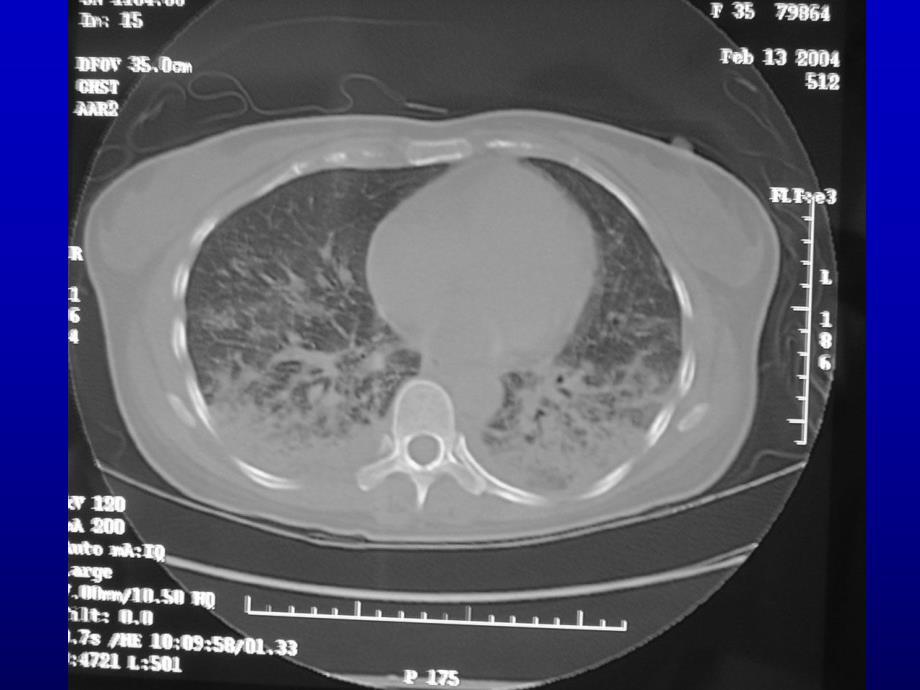

9、有杵状指。X线表现与病程有关,早期以毛玻璃样线表现与病程有关,早期以毛玻璃样改变、颗粒状、结节状影为主,进而可改变、颗粒状、结节状影为主,进而可出现网状、线状阴影,晚期表现为环状出现网状、线状阴影,晚期表现为环状或蜂窝状阴影以及肺容积缩小。另外,或蜂窝状阴影以及肺容积缩小。另外,可有肺门增大,肺门阴影模糊、肺不张,可有肺门增大,肺门阴影模糊、肺不张,胸膜增厚和胸腔积液。胸膜增厚和胸腔积液。类风湿性关节炎系统性红斑狼疮多发性肌炎和皮肌炎白塞病干燥综合征混合性结缔组织病类风湿性关节炎系统性红斑狼疮多发性肌炎和皮肌炎白塞病干燥综合征混合性结缔组织病肺功能表现为限制性的通气障肺功能表现为限制性的通气障

10、碍和弥散功能障碍,通常肺功能改碍和弥散功能障碍,通常肺功能改变先于胸部变先于胸部X线改变。线改变。类风湿性关节炎系统性红斑狼疮多发性肌炎和皮肌炎白塞病干燥综合征混合性结缔组织病某些多发性肌炎患者血清中存在某些多发性肌炎患者血清中存在抗抗J0-1抗体,这些抗体阳性的患者,抗体,这些抗体阳性的患者,与与PM-DM有关的间质性肺疾病(有关的间质性肺疾病(ILD)的发生率相当高,约占的发生率相当高,约占50%。类风湿性关节炎系统性红斑狼疮多发性肌炎和皮肌炎白塞病干燥综合征混合性结缔组织病诊断要点诊断要点l干咳、喘息性咳嗽、杵状指、干咳、喘息性咳嗽、杵状指、Velcro啰音;啰音;l胸片提示间质肺炎、肺